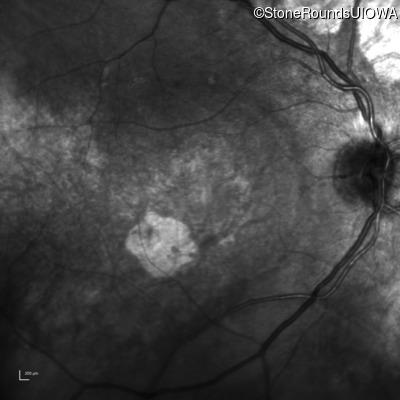

Infrared Fundus Photograph - Right - 20/125 -2

Exemplar